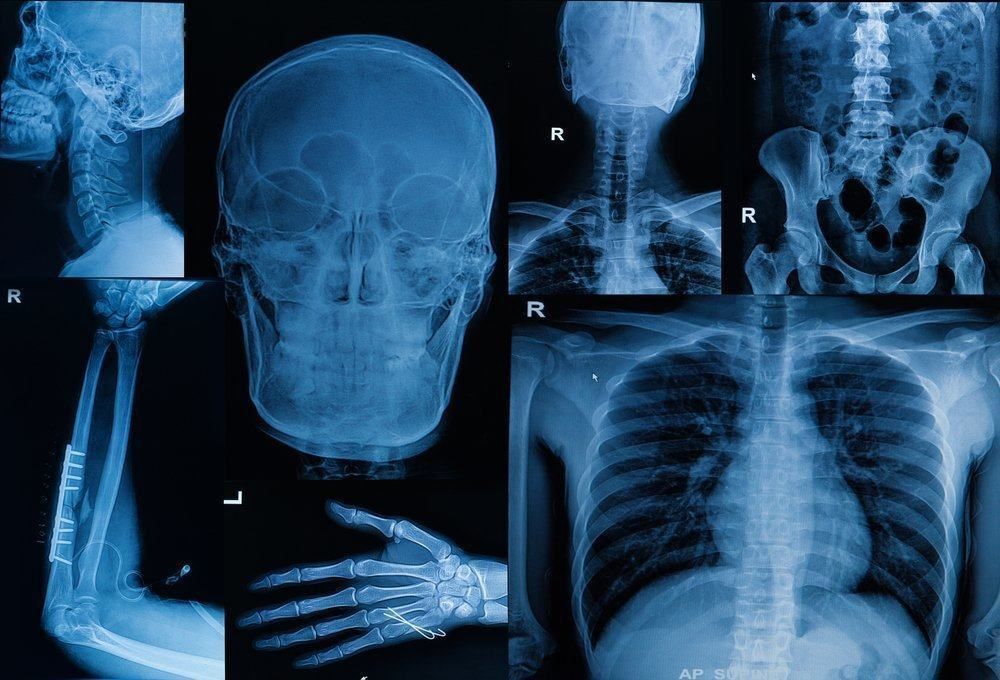

Bone scan atau scan tulang adalah sebuah metode pencitraan yang dilakukan untuk mendiagnosis beberapa jenis penyakit tulang.

Prosedur pencitraan ini menggunakan sedikit bahan radioaktif yang membantu memperlihatkan gambaran jelas kondisi tulang Anda.

Dokter akan menggunakan kamera khusus untuk memindai tulang Anda. Bila ada bagian tulang yang rusak, maka akan muncul titik-titik gelap di gambar.